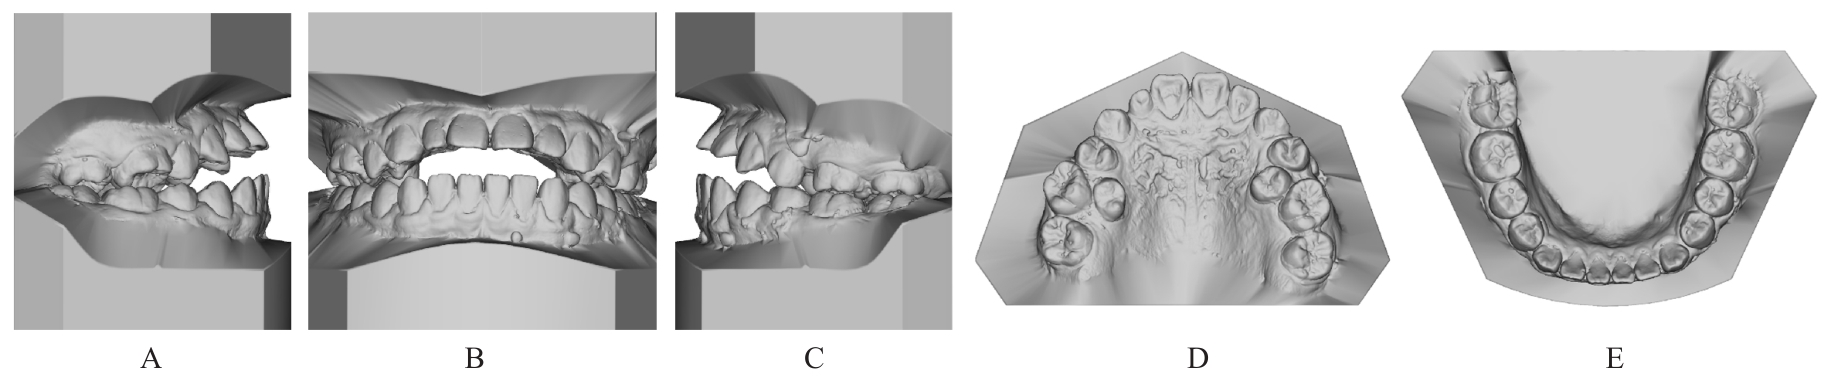

Grade Ⅲ open bite complicated with tongue hypertrophy treated by mandibular incisor extraction:A case report and literature review

Lei TIAN,Yuyan LIU,Yuqing WANG,Zhiyu ZHANG,Xiumei SUN( )

- Department of Orthodontics,Stomatology Hospital,Jilin University,Changchun 130021,China